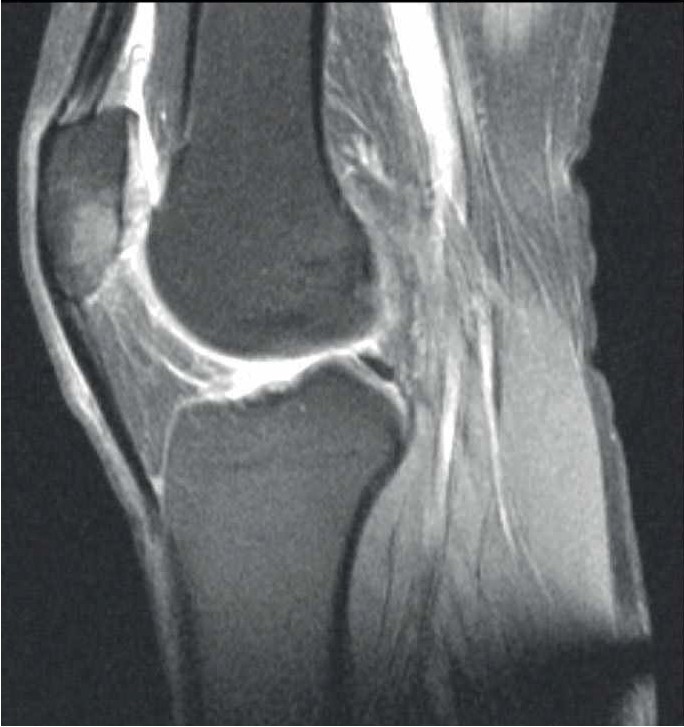

- Женщина А., 27 лет. При обращении жалобы на распирающую, пульсирующую боль в области медиального мыщелка левой бедренной кости и ночную боль (интенсивность – 7 баллов по визуально-аналоговой шкале боли, ВАШ) в левой ноге. Отмечается нарушение опороспособности на левую нижнюю конечность. Соматический и наследственный анамнез не отягощен. В мае 2021 г. перенесла острую респираторную вирусную инфекцию в легкой форме. 06.10.2021 г. выполнена спиральная компьютерная томография (СКТ) левого коленного сустава, обнаружен асептический некроз медиального мыщелка левой бедренной кости (рис. 1А). 25.11.2021 г. выполнены артроскопия левого коленного сустава, декомпрессия очага некроза. Назначено консервативное лечение. 16.01.2022 г. проведена контрольная МРТ – асептический некроз медиального мыщелка левой бедренной кости (см. рис. 1Б).

Рис. 1. СКТ левого коленного сустава у пациентки А. Диагноз: асептический некроз медиального мыщелка левой бедренной кости: 06.10.2021 г. (А), 25.11.2021 г. (Б), эндопротез левого коленного сустава (В).

На контрольном осмотре пациентка отмечает постоянную боль тянущего характера по медиальной поверхности левого коленного сустава, резкую боль (7 баллов по ВАШ) в области медиального мыщелка левой бедренной кости при попытке активного и пассивного сгибания коленного сустава и в области медиального мыщелка левой бедренной кости при осевой нагрузке на левую нижнюю конечность. Отсутствуют улучшения по данным МРТ, увеличивается функциональная недостаточность по клиническим данным.

11.02.2022 г. выполнена имплантация эндопротеза левого коленного сустава с одновременной реконструкцией биологической оси конечности (см. рис. 1В). В послеоперационном периоде на 7-е сутки пациентка отмечает восстановление функции коленного сустава, отсутствие болевого синдрома (1 балл по ВАШ).